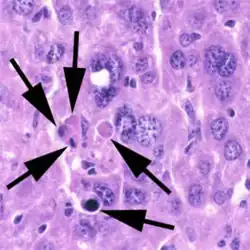

A section of mouse liver showing several apoptotic cells, indicated by arrows

A section of mouse liver stained to show cells undergoing apoptosis (orange)